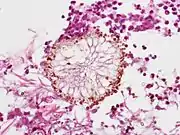

Aspergillus vesicle (HE stain)